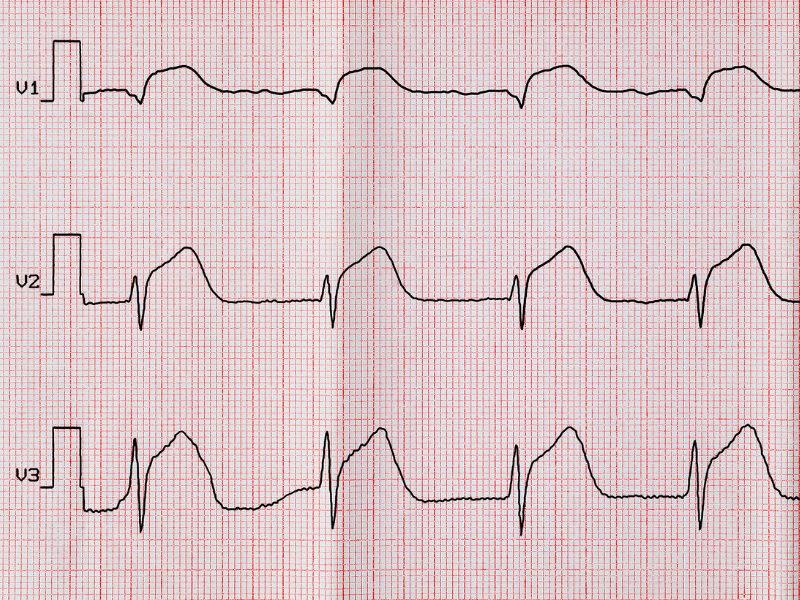

8) Infarto, isquemia e intervalo QT

Nesta última, porém não menos importante etapa da avaliação do ECG, vamos descrever e interpretar aspectos relacionados ainda à ativação ventricular e avaliar as alterações possíveis da repolarização ventricular que possam indicar a presença de patologias.

Infarto

A avaliação de infarto requer atenção especial. Na verdade, quando falamos infarto do miocárdio podemos estar nos referindo ao infarto agudo (ou IAM), em que estamos diante de uma emergência e ações imediatas são necessárias, ou podemos estar diante de um infarto antigo, na grande maioria das vezes num paciente que se apresenta de forma assintomática.

O diagnóstico de infarto antigo ou necrose miocárdica é feito por meio da avaliação dos complexos QRS na busca de ondas Q patológicas. Elas necessariamente aparecerão em derivações contíguas que compõem as chamadas paredes ou áreas do coração. Por exemplo, se encontramos ondas Q patológicas das derivações DII, DIII e aVF, podemos dizer que temos uma área de necrose ou infarto em parede inferior.

Existem outros achados que podem estar relacionados à presença de infarto prévio, como baixa progressão da onda R no plano horizontal, sugerindo área eletricamente inativa anterior, ou mesmo sinais específicos, como o de Cabrera, que aparece nos casos de pacientes portadores de bloqueio de ramo esquerdo.

Já o diagnóstico eletrocardiográfico de infarto agudo do miocárdio é realizado por meio da avaliação de supradesnivelamentos do segmento ST também em derivações contíguas, indicando uma insuficiência coronariana (ou dificuldade de entrega de sangue ao músculo cardíaco) que acomete a parede do miocárdio de forma transmural, ou seja, desde o epicárdio até o endocárdio.

Figura 7: IAM de parede anterosseptal: elevação do segmento ST de V1 a V3.

Figura 7: IAM de parede anterosseptal: elevação do segmento ST de V1 a V3.

Figura 6: Bloqueio de ramo esquerdo. A definição de bloqueio de ramo envolve a ocorrência de complexos QRS com duração igual ou maior a 120ms e com morfologia indicando acometimento do ramo esquerdo ou direito. Figura 7: IAM de parede anterosseptal: elevação do segmento ST de V1 a V3.

Figura 7: IAM de parede anterosseptal: elevação do segmento ST de V1 a V3. Figura 8: Sempre faça o ECG de controle após a reversão de uma taquicardia supraventricular paroxística.